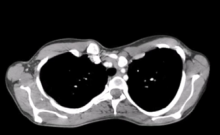

The authors present a case of mitral valve (MV) repair combined with pectus excavatum repair in a highly symptomatic 28-year-old woman. Her preoperative transesophageal (TEE) echo showed severe mitral insufficiency, and her preoperative computed tomography (CT) scan showed a Haller index of 16.3 and heart displacement to the left.

A six-month follow-up CT scan showed nice functional and aesthetic results.